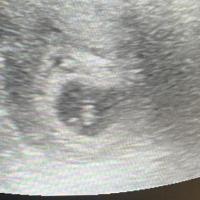

Первое УЗИ при беременности: 5-6 недель, сердцебиение

20.11.2025

11 лайков

вчера была на узи. сказали точно 4нед есть. 🙏 расти мой карапуз❤️

06.11.2025

4 комментария

8 лайков